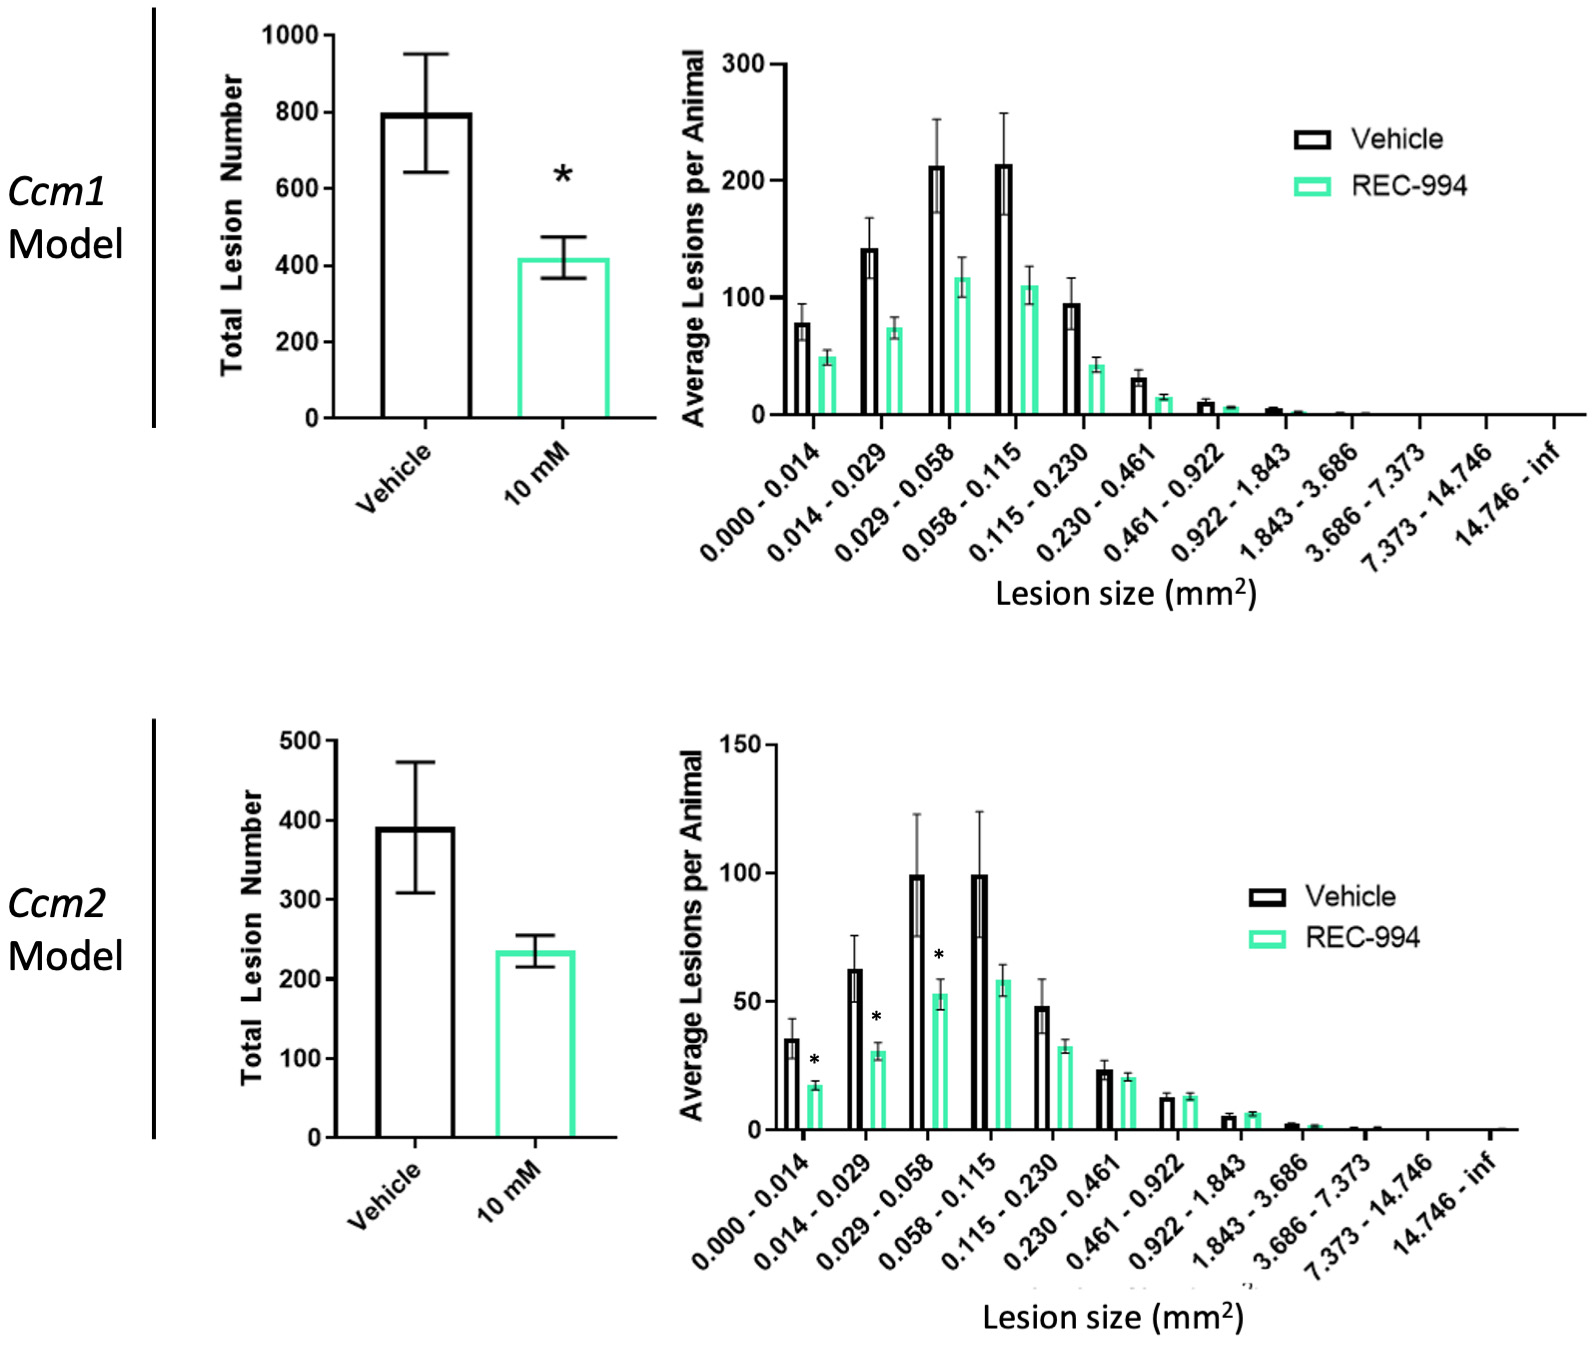

•Five phase 2 clinical-stage programs with multiple upcoming data readouts expected, including REC-994 in cerebral cavernous malformation (CCM) in Q3 2024, REC-2282 in neurofibromatosis type 2 (NF2) in Q4 2024, REC-4881 in familial adenomatous polyposis (FAP) in H1 2025, and REC-4881 in AXIN1 or APC mutant solid tumors in H1 2025